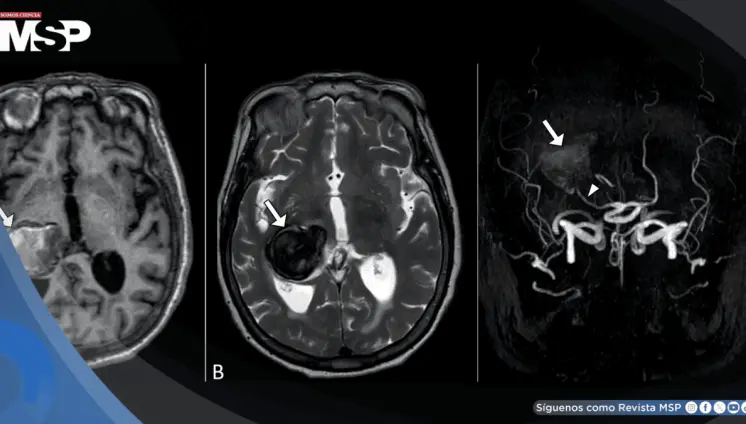

Dolor de cabeza y visión borrosa revelaron un aneurisma cerebral gigante en un hombre de 64 años